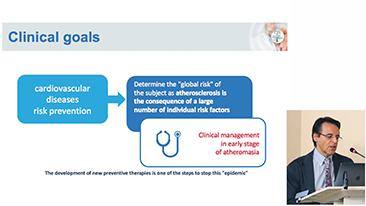

Lingkungan medis saat ini telah menjadi lebih kompleks, dengan peningkatan jumlah kasus yang sulit dan beban kerja.